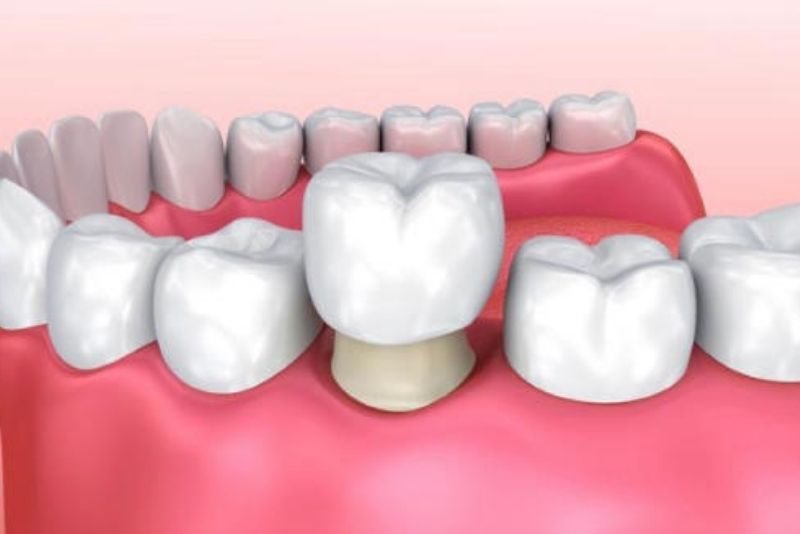

Bọc sứ bảo vệ cấu trúc răng

2. Các trường hợp nên bọc răng sứ

Khi răng bị sâu vỡ lớn, đã chữa tủy, ố vàng nặng không tẩy trắng được, sứt mẻ, mòn men răng, răng thưa/hô/lệch nhẹ, hoặc mất răng (làm cầu răng) cần bọc mão sứ để phục hồi hình dáng, chức năng ăn nhai và thẩm mỹ.

Răng sau khi lấy tủy rất giòn và dễ nứt vỡ do mất nguồn nuôi dưỡng, vì vậy nên ưu tiên răng toàn sứ như Zirconia, Cercon, Emax để bảo vệ răng tối ưu. Các dòng sứ này có độ cứng cao, chịu lực tốt, ôm sát cùi răng và không gây đen viền nướu, khôi phục ăn nhai bền chắc và thẩm mỹ tự nhiên.

Việc lựa chọn loại sứ cụ thể sẽ dựa trên vị trí răng (răng cửa hay răng hàm), mức độ tổn thương và lực nhai, và cần được bác sĩ thăm khám trực tiếp để chỉ định phù hợp.